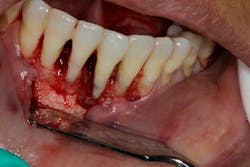

- Ensure tooth does not have a root fracture and check/refer for endodontic treatment if tooth is nonvital (figure 1)

- Proper surgical technique including incision, flap design, and complete detoxification of bony defect and root apices (figures 3 and 3a)